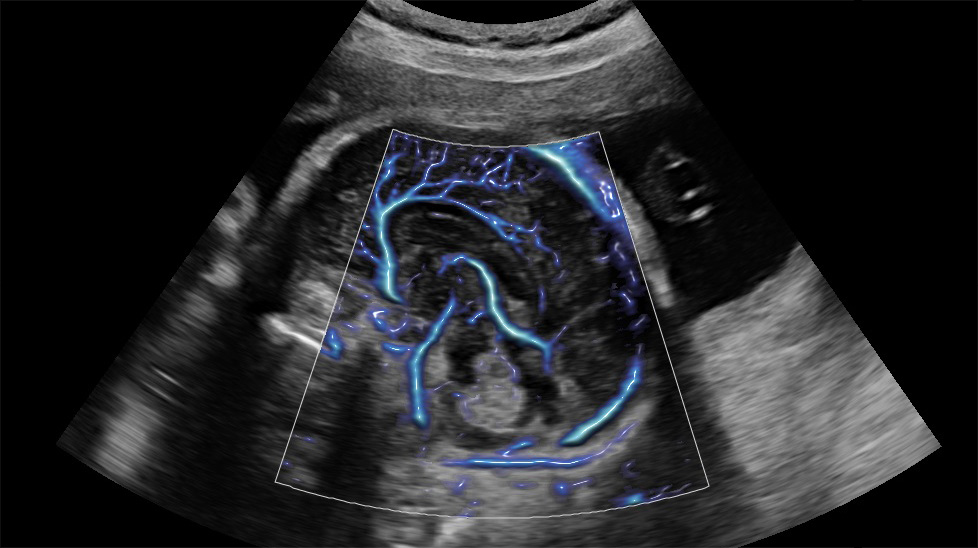

Le innovative tecnologie proprietarie di Samsung supportano la diagnosi assicurando un maggiore dettaglio e velocizzano i flussi di lavoro.